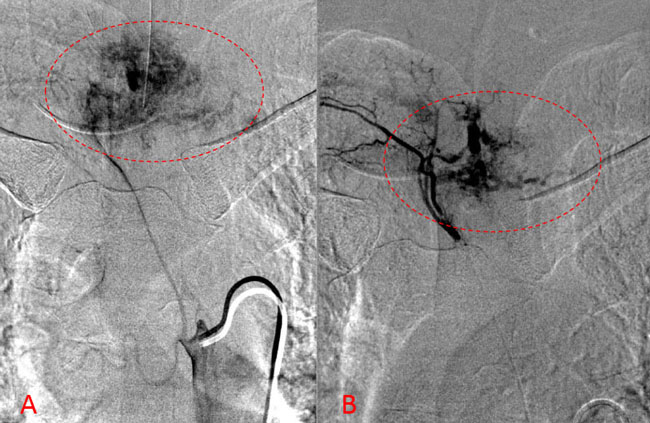

Spinal angiography showed a very hypervascular lesion fed predominantly by the right supreme intercostal artery (Figure 2. A, B).

Figure 2. (A, B) Selective angiography of the right supreme intercostal artery demonstrates extensive hypervascularity of this aggressive T3 hemangioma.

No spinal artery contributions were found to arise from this right T1-T3 pedicle. Superselective WADA testing was performed with Brevital injected through the microcatheter, which failed to elicit changes in the intraoperative monitoring, confirming safety to proceed with devascularization of this pedicle and tumor. This was performed with 100-300 micron particles achieving an excellent devascularization (Figure 3. A, B).